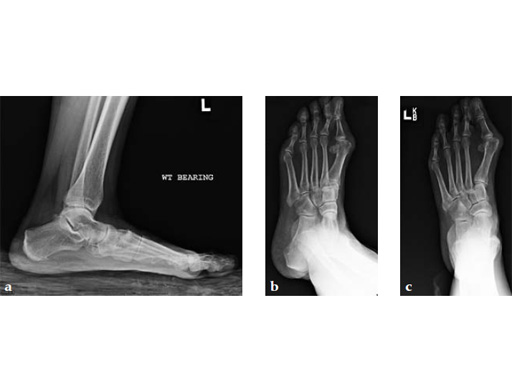

Case 8: VA -locking X-plate

A 38-year-old man fell from a 7-foot height while at work. The patient was seen at an urgent care facility and diagnosed with an ankle sprain. He was placed in a stirrup brace and instructed to bear weight as tolerated.

After 4 months the patient presented for a second opinion. His complaint was pain to the lateral column and subtalar joint. The preoperative lateral x-ray is notable for a malunited talar neck fracture with subluxation of the subtalar joint. The disproportion of the medial and lateral columns and a cavovarus position of the foot are seen on both the AP and lateral views. The degenerative changes at both the talonavicular and subtalar joints are significant.

The patient was treated with arthrodesis of the talonavicular and subtalar joints. The compression/ distraction device was used to restore the length of the medial column. The articular surface of the subtalar joint was prepared arthroscopically. The talonavicular joint was debrided then packed with a tricalcium matrix. Length was maintained using a locking X-plate. The subtalar joint was then fixed with a 6.5 mm headless compression screw.

The patient returned to work 3 months after surgery. He wears an ankle brace when on uneven surfaces. His lateral column and subtalar pain have resolved.